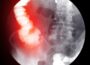

Για τη διάγνωση εμφράγματος του μυοκαρδίου, οι γιατροί αξιοποιούν συνδυασμό εξετάσεων. Από τις βασικές είναι το ηλεκτροκαρδιογράφημα (ΗΚΓ), το οποίο βοηθά στην εκτίμηση της ηλεκτρικής λειτουργίας της καρδιάς. Σημαντικό ρόλο έχουν και οι εξετάσεις αίματος, καθώς δείχνουν δείκτες βλάβης του καρδιακού μυός, όπως η τροπονίνη, η κρεατινική κινάση και άλλοι. Η ηχωκαρδιογραφία αποτελεί επίσης βασική μέθοδο, επειδή επιτρέπει την αξιολόγηση της κατάστασης του μυοκαρδίου και τον έλεγχο του μεγέθους και της λειτουργίας των κοιλοτήτων της καρδιάς. Όταν υπάρχει αμφιβολία για την κατάσταση των στεφανιαίων αγγείων, μπορεί να γίνει στεφανιογραφία, μια επεμβατική εξέταση που εκτιμά τα αγγεία της καρδιάς και εντοπίζει στενώσεις ή αποφράξεις. Επιπλέον, αξιόπιστη εξέταση είναι και η δοκιμασία κόπωσης σε εργομετρικό ποδήλατο, όπου ο ασθενής κάνει πετάλι ενώ παρακολουθείται το ΗΚΓ. Ο συνδυασμός αυτών των ελέγχων βοηθά στην επιβεβαίωση της διάγνωσης, στην εκτίμηση της βαρύτητας και στην επιλογή του κατάλληλου θεραπευτικού πλάνου.